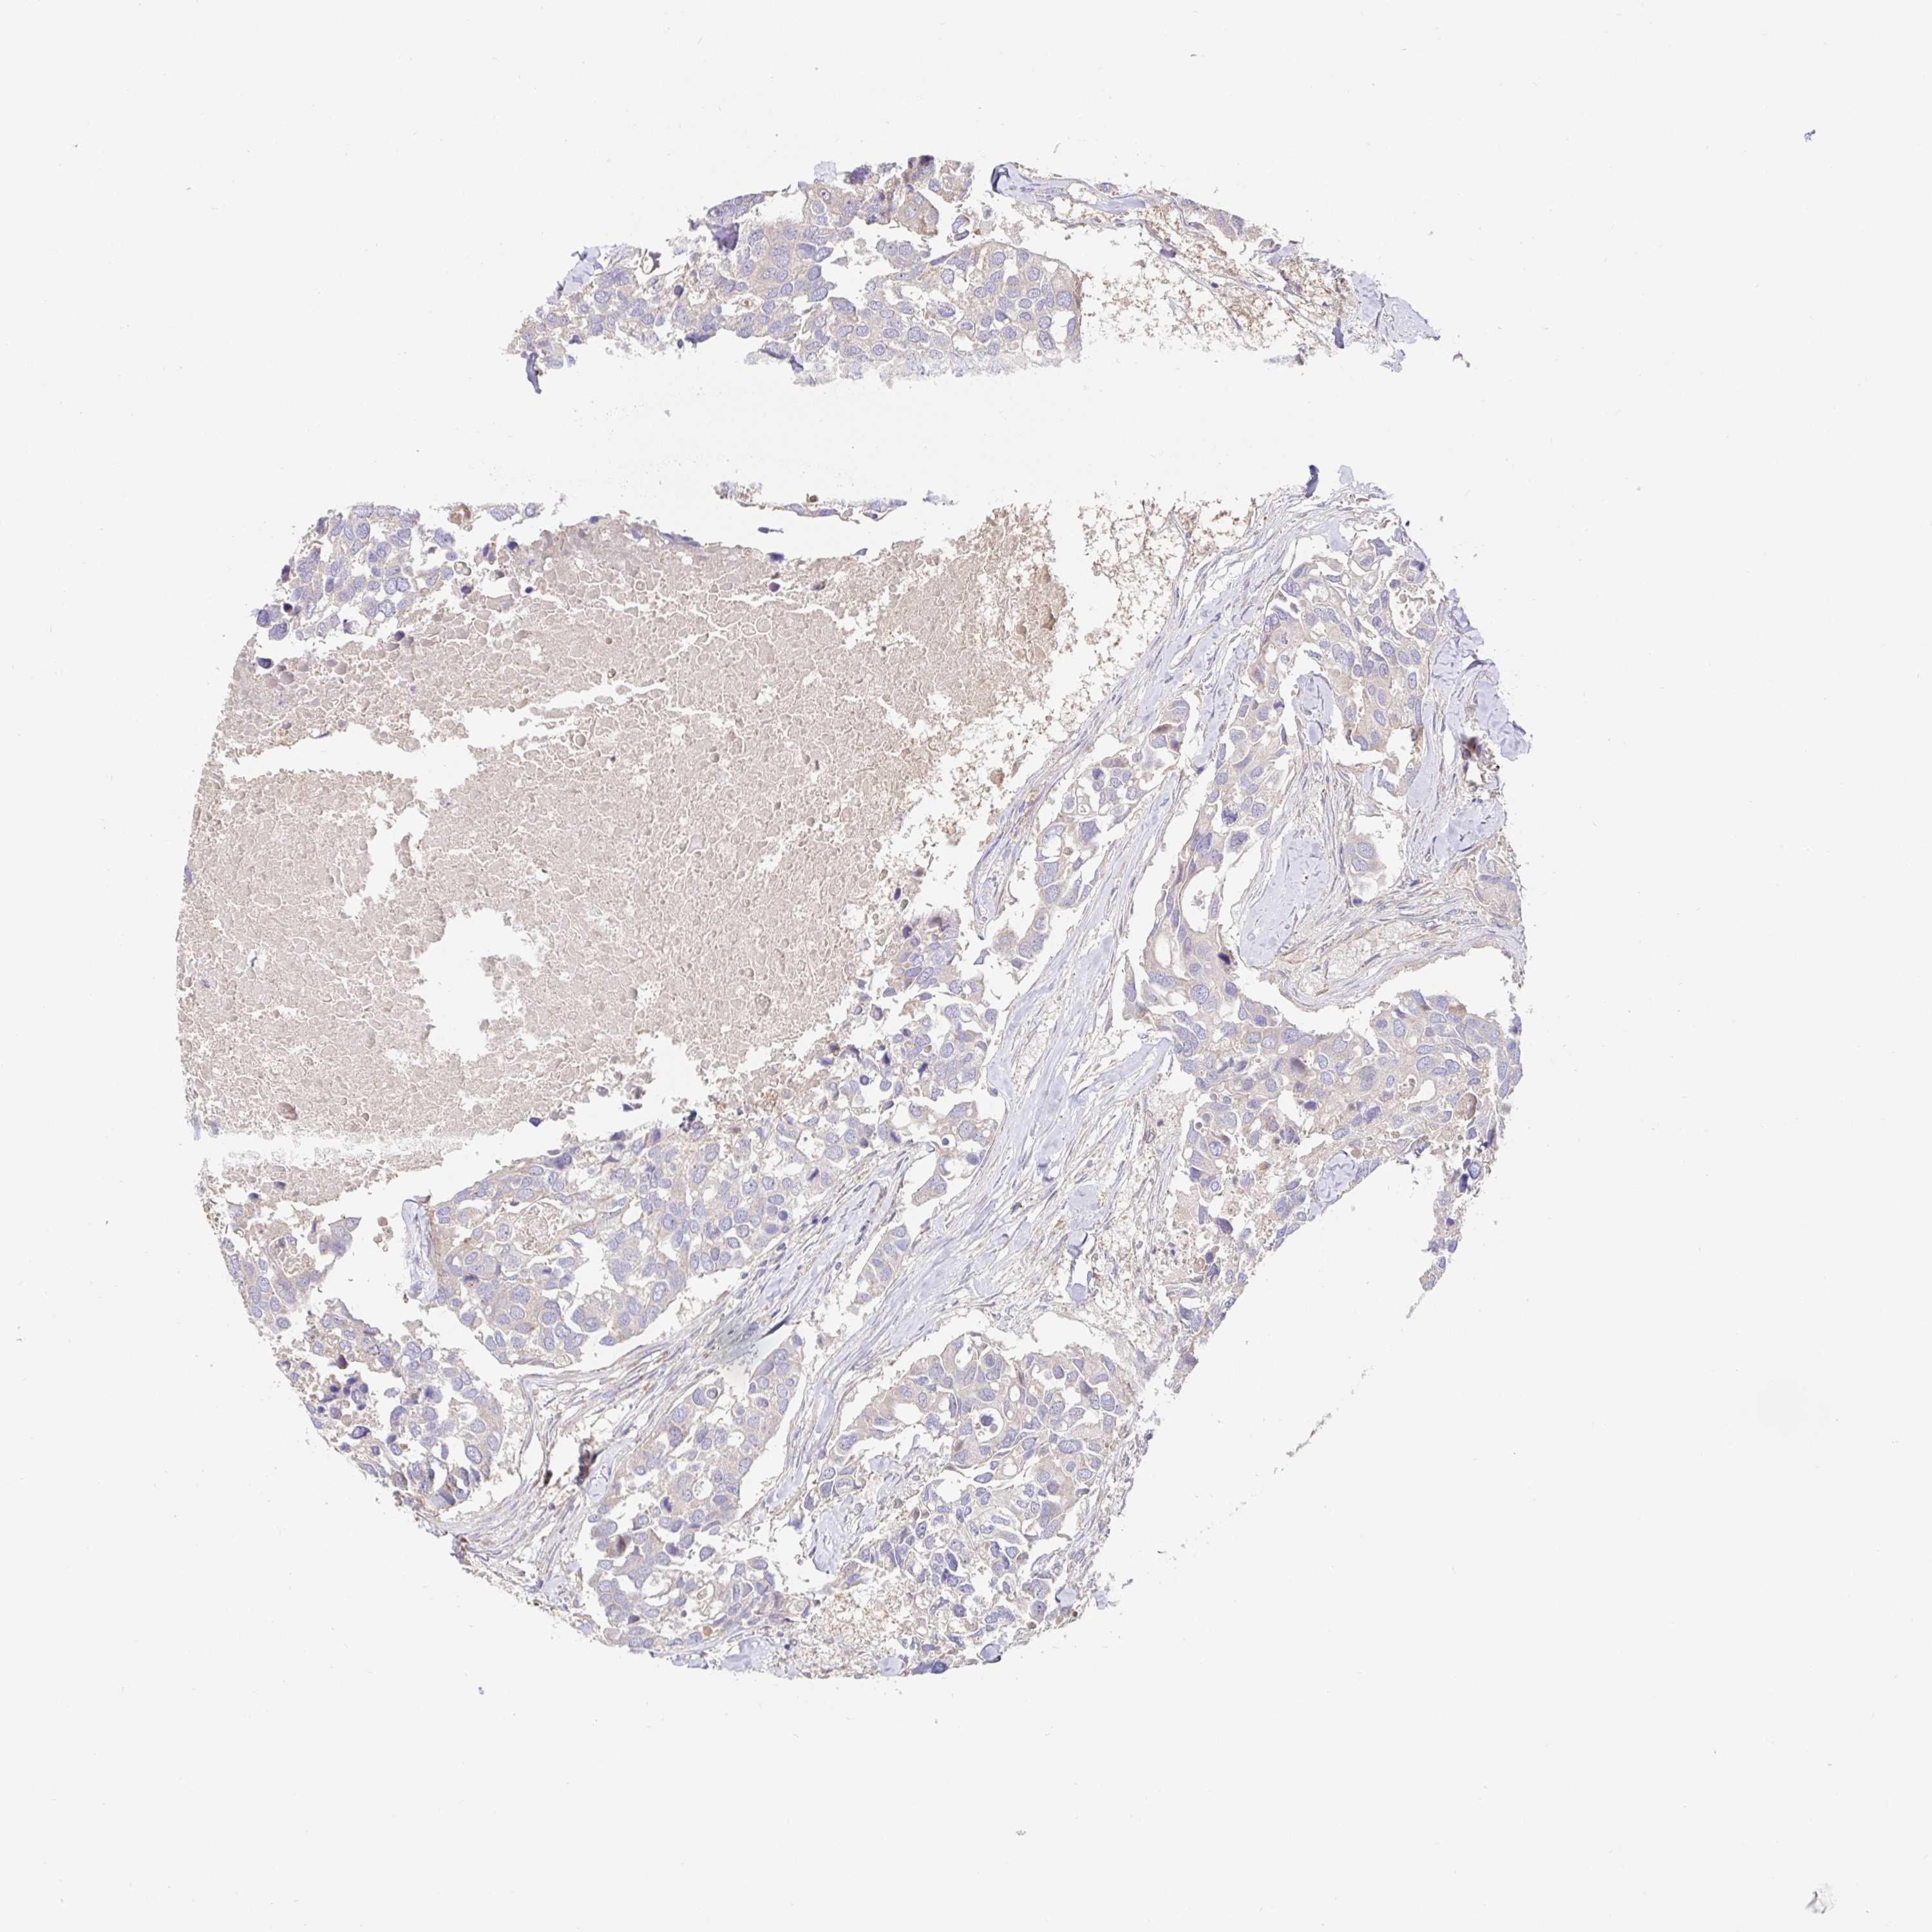

CANCER BREAST CANCER Show tissue menu

BRCA TCGA BRCA VALIDATION PROTEIN EXPRESSION

HAGH is not prognostic in Breast Invasive Carcinoma (TCGA)